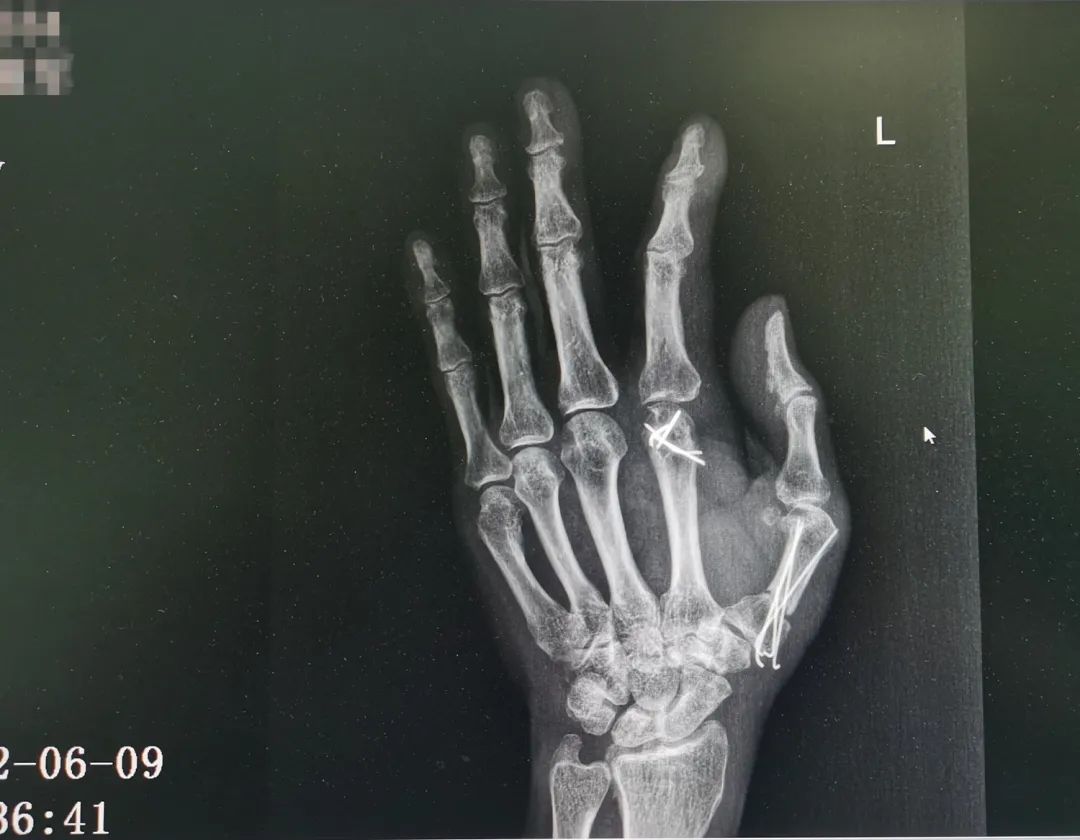

△圖為:患者術(shù)前及術(shù)后復(fù)查X光片對(duì)比

此次復(fù)查,王瑞良主任告訴楊大叔,目前他恢復(fù)情況良好,后續(xù)取出內(nèi)固定釘,并進(jìn)行肌腱松解手術(shù),加上術(shù)后正確的功能康復(fù)鍛煉,大拇指就能重新自由活動(dòng),左手功能達(dá)到基本正常。